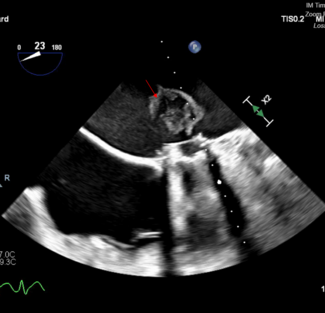

Adamantios Tsangaris, MD; Ganesh Raveendran, MD; Gurumurthy Hiremath, MD

A 49-year-old man presented late with an anterior wall myocardial infarction (MI) status post-primary coronary intervention of the left anterior descending artery that resulted in no reflow of the vessel. The patient was transferred to our...